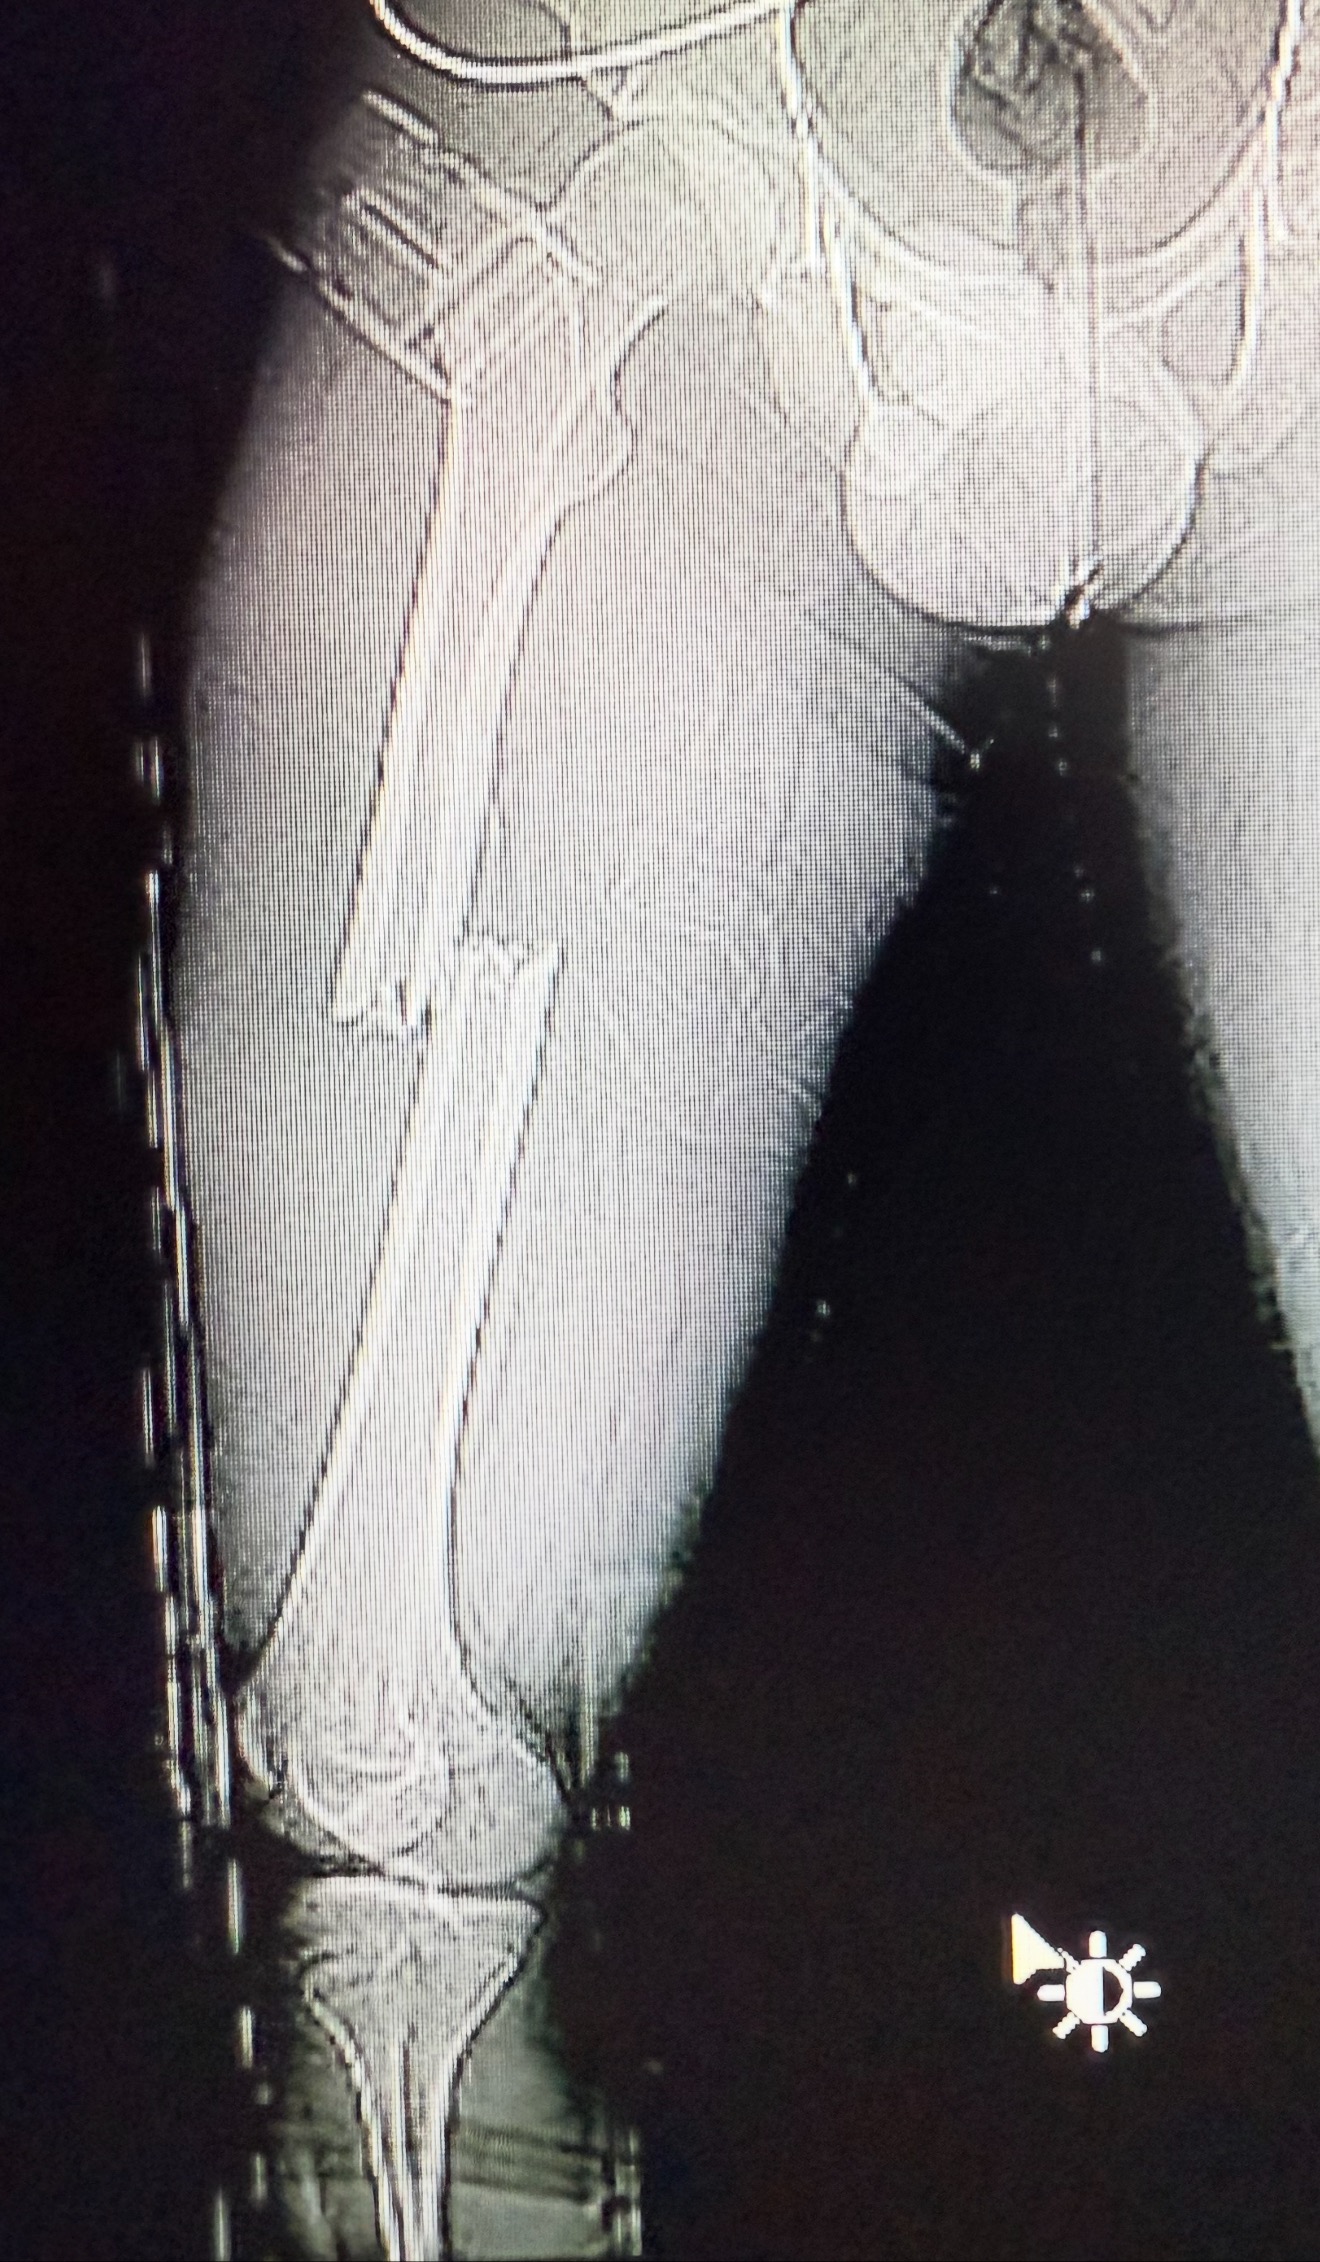

He suffered a severely broken femur—his thigh bone was split in half—and underwent emergency surgery to insert rods and pins into his leg. He is currently still in the hospital, and his next step is intensive, inpatient physical therapy to help him walk again.